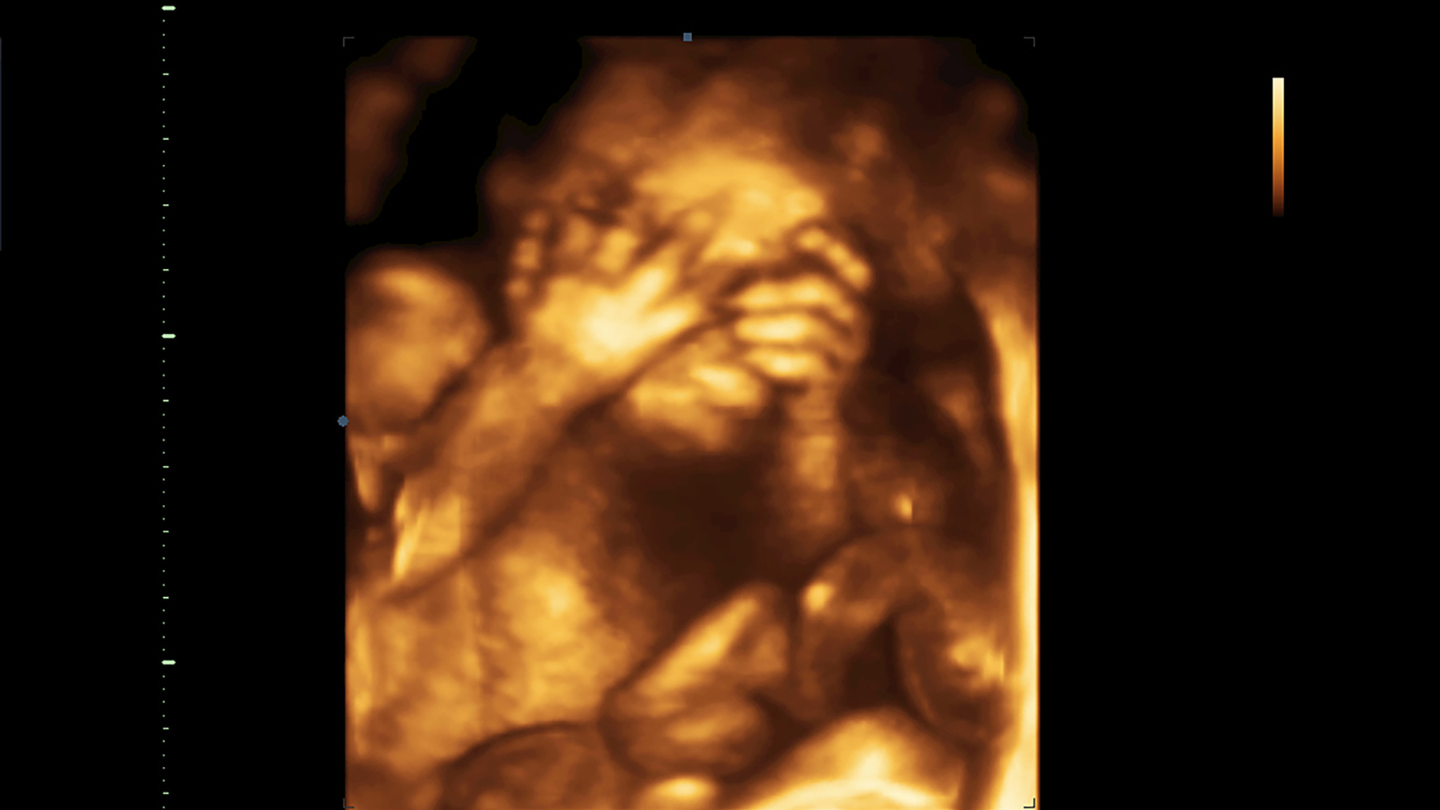

Bước sang tháng thứ 6 của thai kỳ, cơ thể mẹ và thai nhi đã có những thay đổi quan trọng, thể hiện rõ qua các đặc điểm phát triển sau đây:

- Các cơ quan quan trọng của thai nhi đã hình thành gần hoàn chỉnh.

- Nguy cơ sảy thai thấp hơn hẳn so với 3 tháng đầu.

- Tử cung phát triển ổn định, bảo vệ thai tốt hơn.